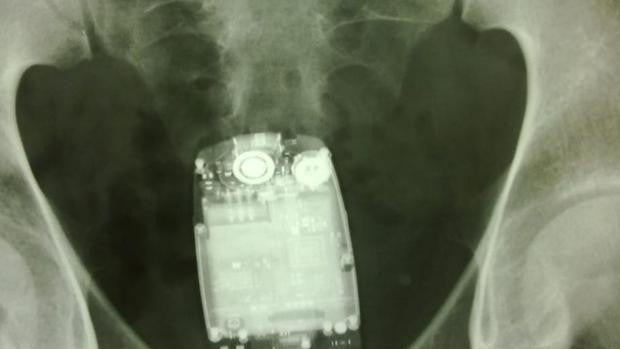

24/02/2022 19:35h. SUCESOS Desde suelas de zapatos al cuerpo, así se esconden los teléfonos móviles para colarlos en la cárcel de Huelva M. Rosa Font